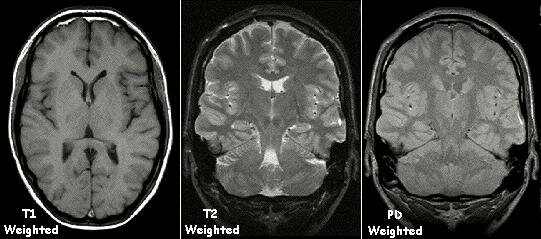

• Resonación magnética - MRI

Resonación magnética - MRI

En el año 1971, el doctor Raymond Damadian presento su descubrimiento en como la resonancia magnética es capaz de detectar enfermedades puesto a que distintos tipos de tejidos emiten señales que varían en duración con respuesta al campo magnético. El primer resonador magnético seria creado al próximo año.